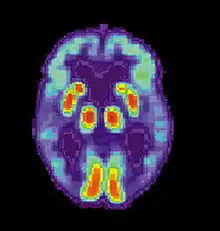

Neural systems used by procedural memory are commonly targeted by Human Immunodeficiency Virus; the striatum being the structure most notably affected.[64] MRI studies have even shown white matter irregularity and basal ganglia subcortical atrophy in these vital areas necessary for both procedural memory and motor-skill.[65] Applied research using various procedural memory tasks such as the Rotary pursuit, Mirror star tracing and Weather prediction tasks have shown that HIV positive individuals perform worse than HIV negative participants suggesting that poorer overall performance on tasks is due to the specific changes in the brain caused by the disease.[66]